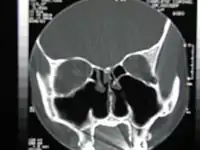

![]() CT scan of the nose after total bilateral turbinectomy | |